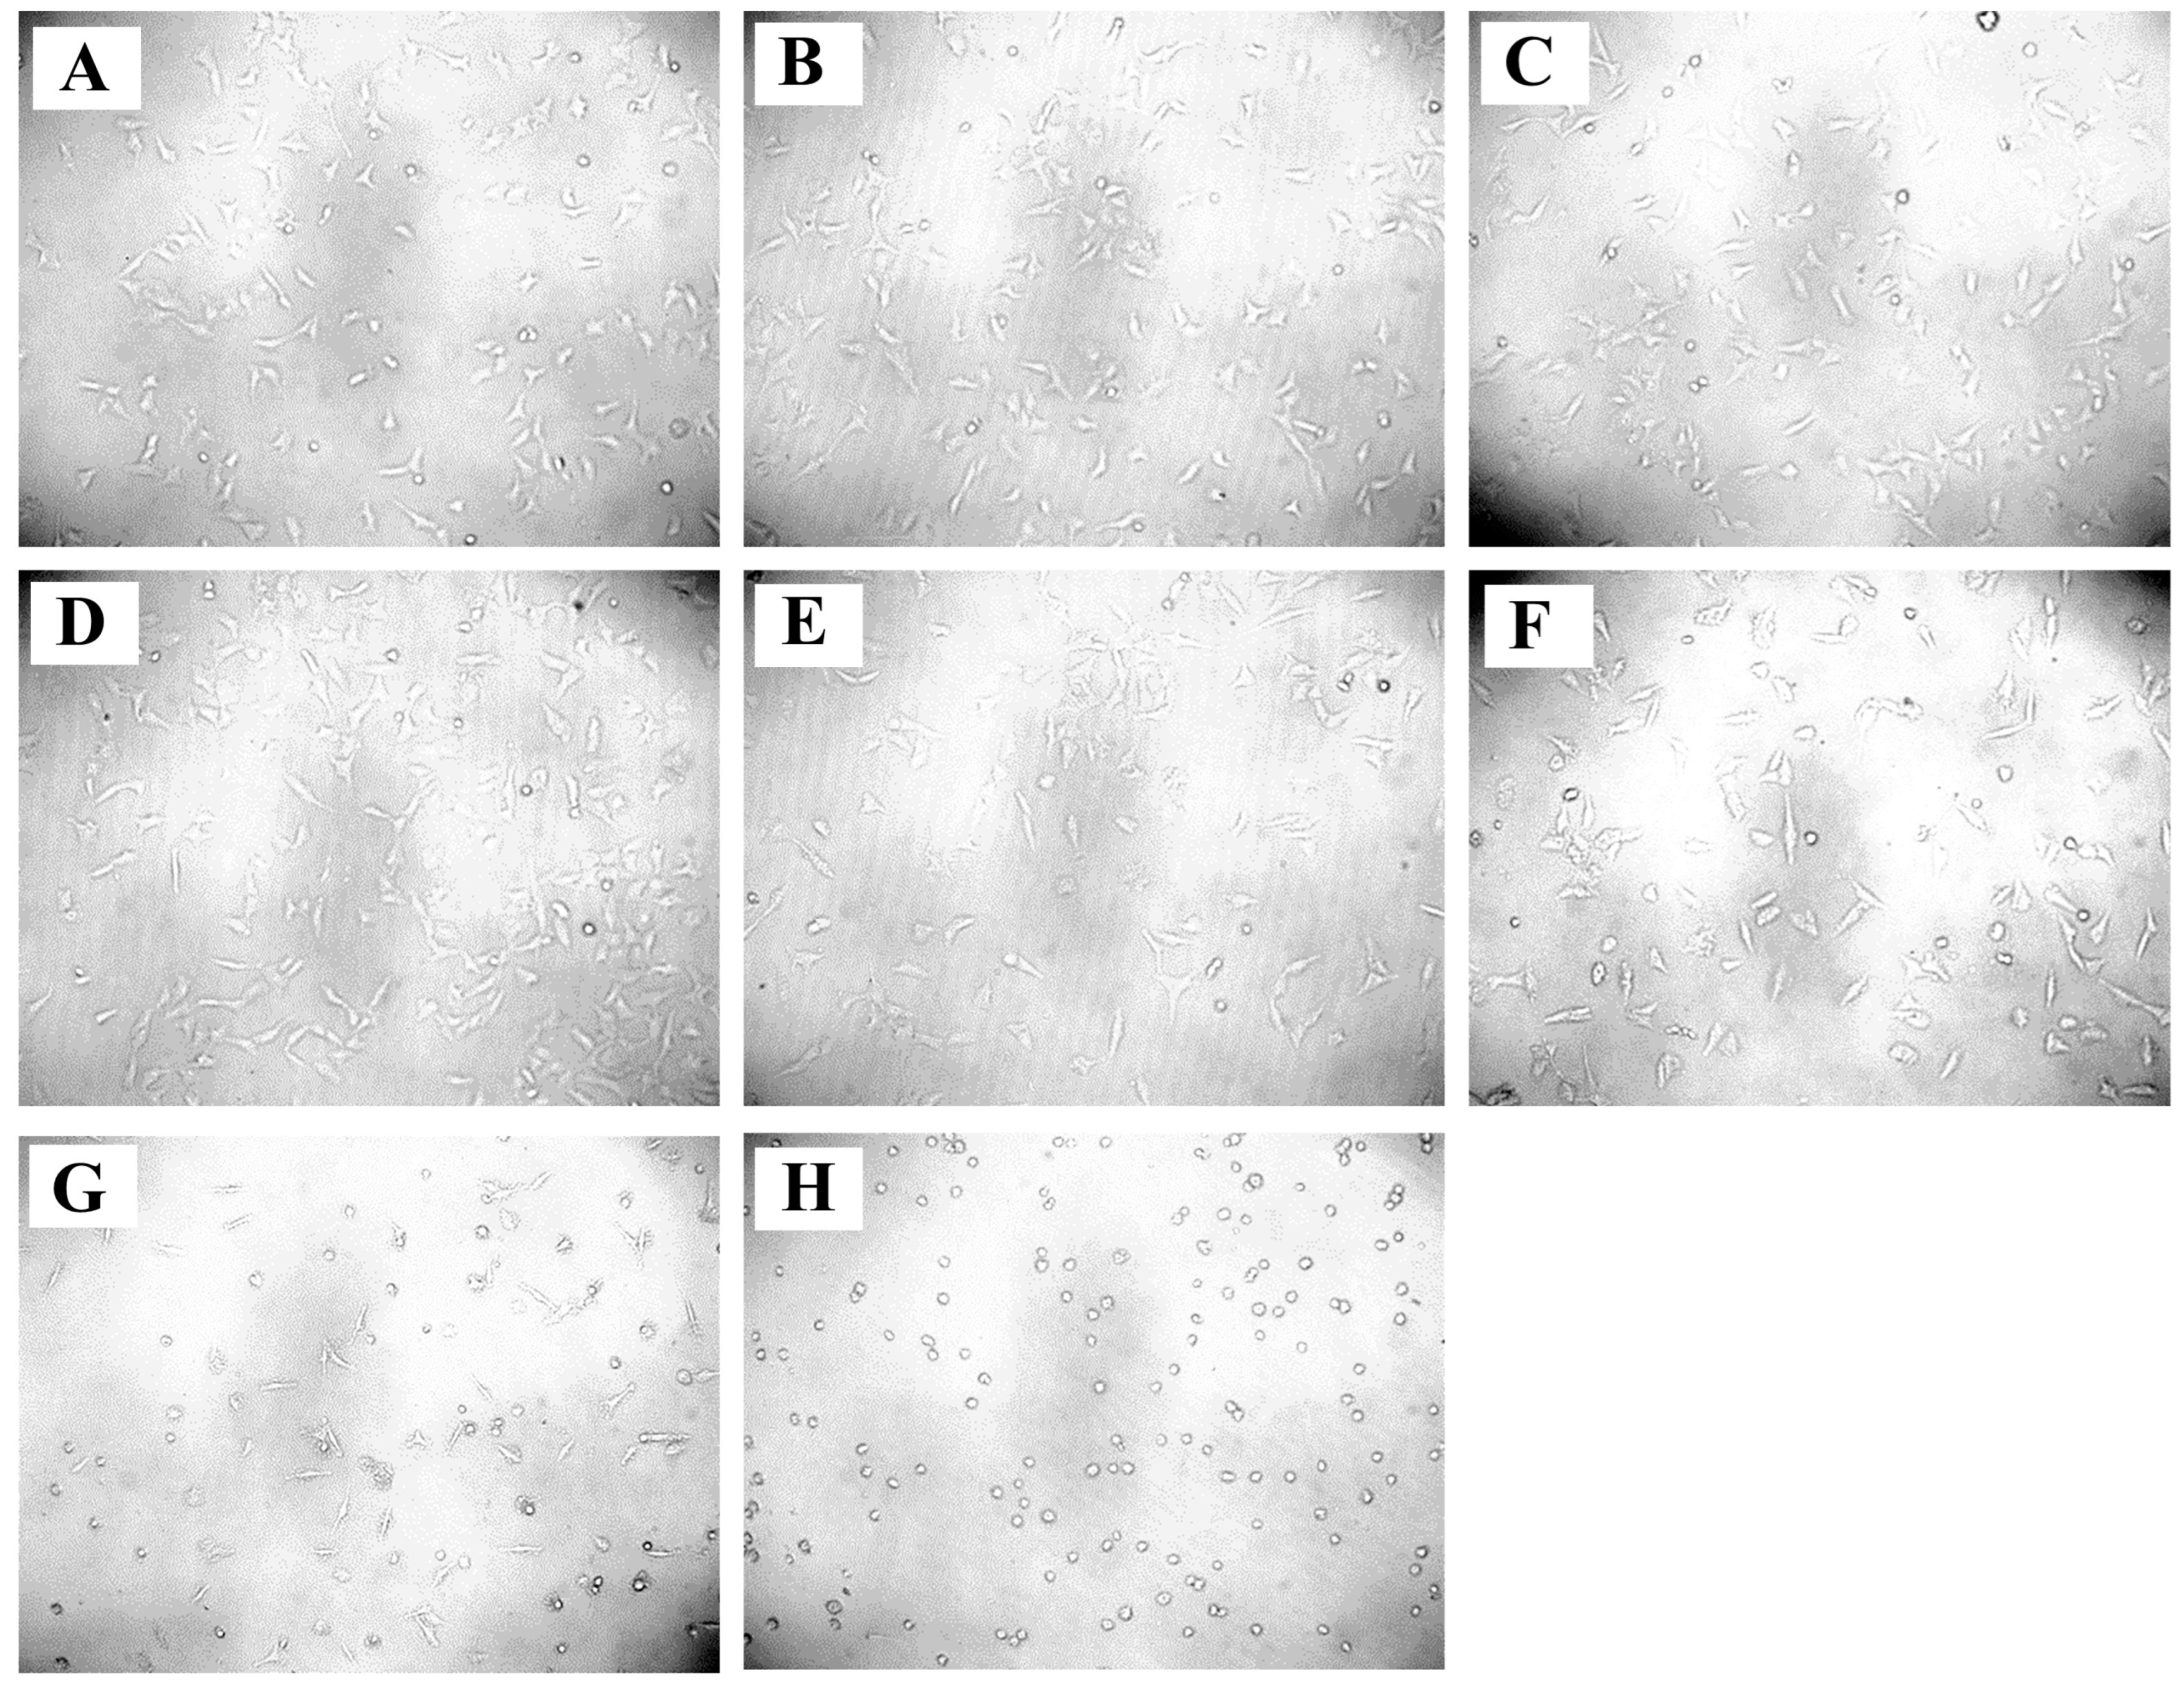

2.7. Anticancer Activity of A. racemosus Crude Extract

2.8. Impact on Cell Cycle Regulation